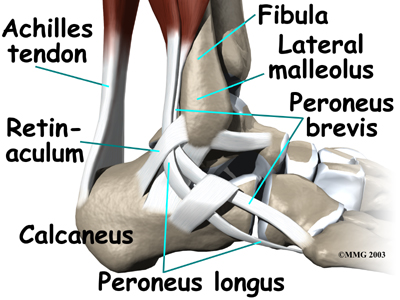

The peroneals are two muscles and their tendons that lie along the outside of the lower leg bone (the fibula) and cross behind the lateral malleolus (the outer ankle bone). The term medial refers to a point closer to the center of the body. So the ankle bump on the inside edge of the ankle (closest to your other ankle) is the medial malleolus. The term lateral refers to structures furthest from the center. Major muscles that support the lateral part of the ankle are the peroneus longus and the peroneus brevis.

The tendons of these two muscles pass together in a groove behind the lateral malleolus. (Tendons attach muscles to bones.) The tendons are kept within the groove by a sheath that forms a tunnel around the tendons. The surface of the tunnel is reinforced by a band of tissue called a retinaculum. Contracting the peroneal muscles makes the tendons glide in the groove like a pulley. The pulley action causes the foot to point (plantarflexion) and (eversion).

The connects to a bump on the base of the fifth metatarsal. This spot can be felt midway down the outer edge of the foot.

The lies behind and below the peroneus brevis tendon. It wraps down and under the foot by way of the cuboid bone, the outer tarsal bone just in front of the heelbone (the calcaneus). The peroneus longus tendon angles forward under the sole of the foot and connects to the bottom of the main bone of the big toe. This tendon stabilizes the arch of the foot when walking.